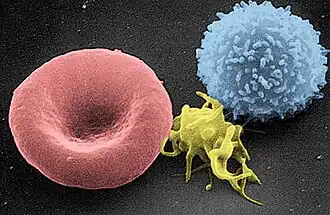

Red blood cells (RBCs), referred to as erythrocytes (from Ancient Greek erythros 'red' and kytos 'hollow vessel', with -cyte translated as 'cell' in modern usage) in academia and medical publishing, also known as red cells,[1] erythroid cells, and rarely haematids, are the most common type of blood cell and the vertebrate's principal means of delivering oxygen (O2) to the body tissues—via blood flow through the circulatory system.[2] Erythrocytes take up oxygen in the lungs, or in fish the gills, and release it into tissues while squeezing through the body's capillaries.

The cytoplasm of a red blood cell is rich in hemoglobin (Hb), an iron-containing biomolecule that can bind oxygen and is responsible for the red color of the cells and the blood. Each human red blood cell contains approximately 270 million hemoglobin molecules.[3] The cell membrane is composed of proteins and lipids, and this structure provides properties essential for physiological cell function such as deformability and stability of the blood cell while traversing the circulatory system and specifically the capillary network.

In humans, mature red blood cells are flexible biconcave disks. They lack a cell nucleus (which is expelled during development) and organelles, to accommodate maximum space for hemoglobin; they can be viewed as sacks of hemoglobin, with a plasma membrane as the sack. Approximately 2.4 million new erythrocytes are produced per second in human adults.[4] The cells develop in the bone marrow and circulate for about 100–120 days in the body before their components are recycled by macrophages. Each circulation takes about 60 seconds (one minute).[5] Approximately 84% of the cells in the human body are the 20–30 trillion red blood cells.[6][7][8][9] Nearly half of the blood's volume (40% to 45%) is red blood cells.

Adult humans have roughly 20–30 trillion red blood cells at any given time, constituting approximately 70% of all cells by number.[21] Women have about 4–5 million red blood cells per microliter (cubic millimeter) of blood and men about 5–6 million; people living at high altitudes with low oxygen tension will have more. Red blood cells are thus much more common than the other blood particles: there are about 4,000–11,000 white blood cells and about 150,000–400,000 platelets per microliter.